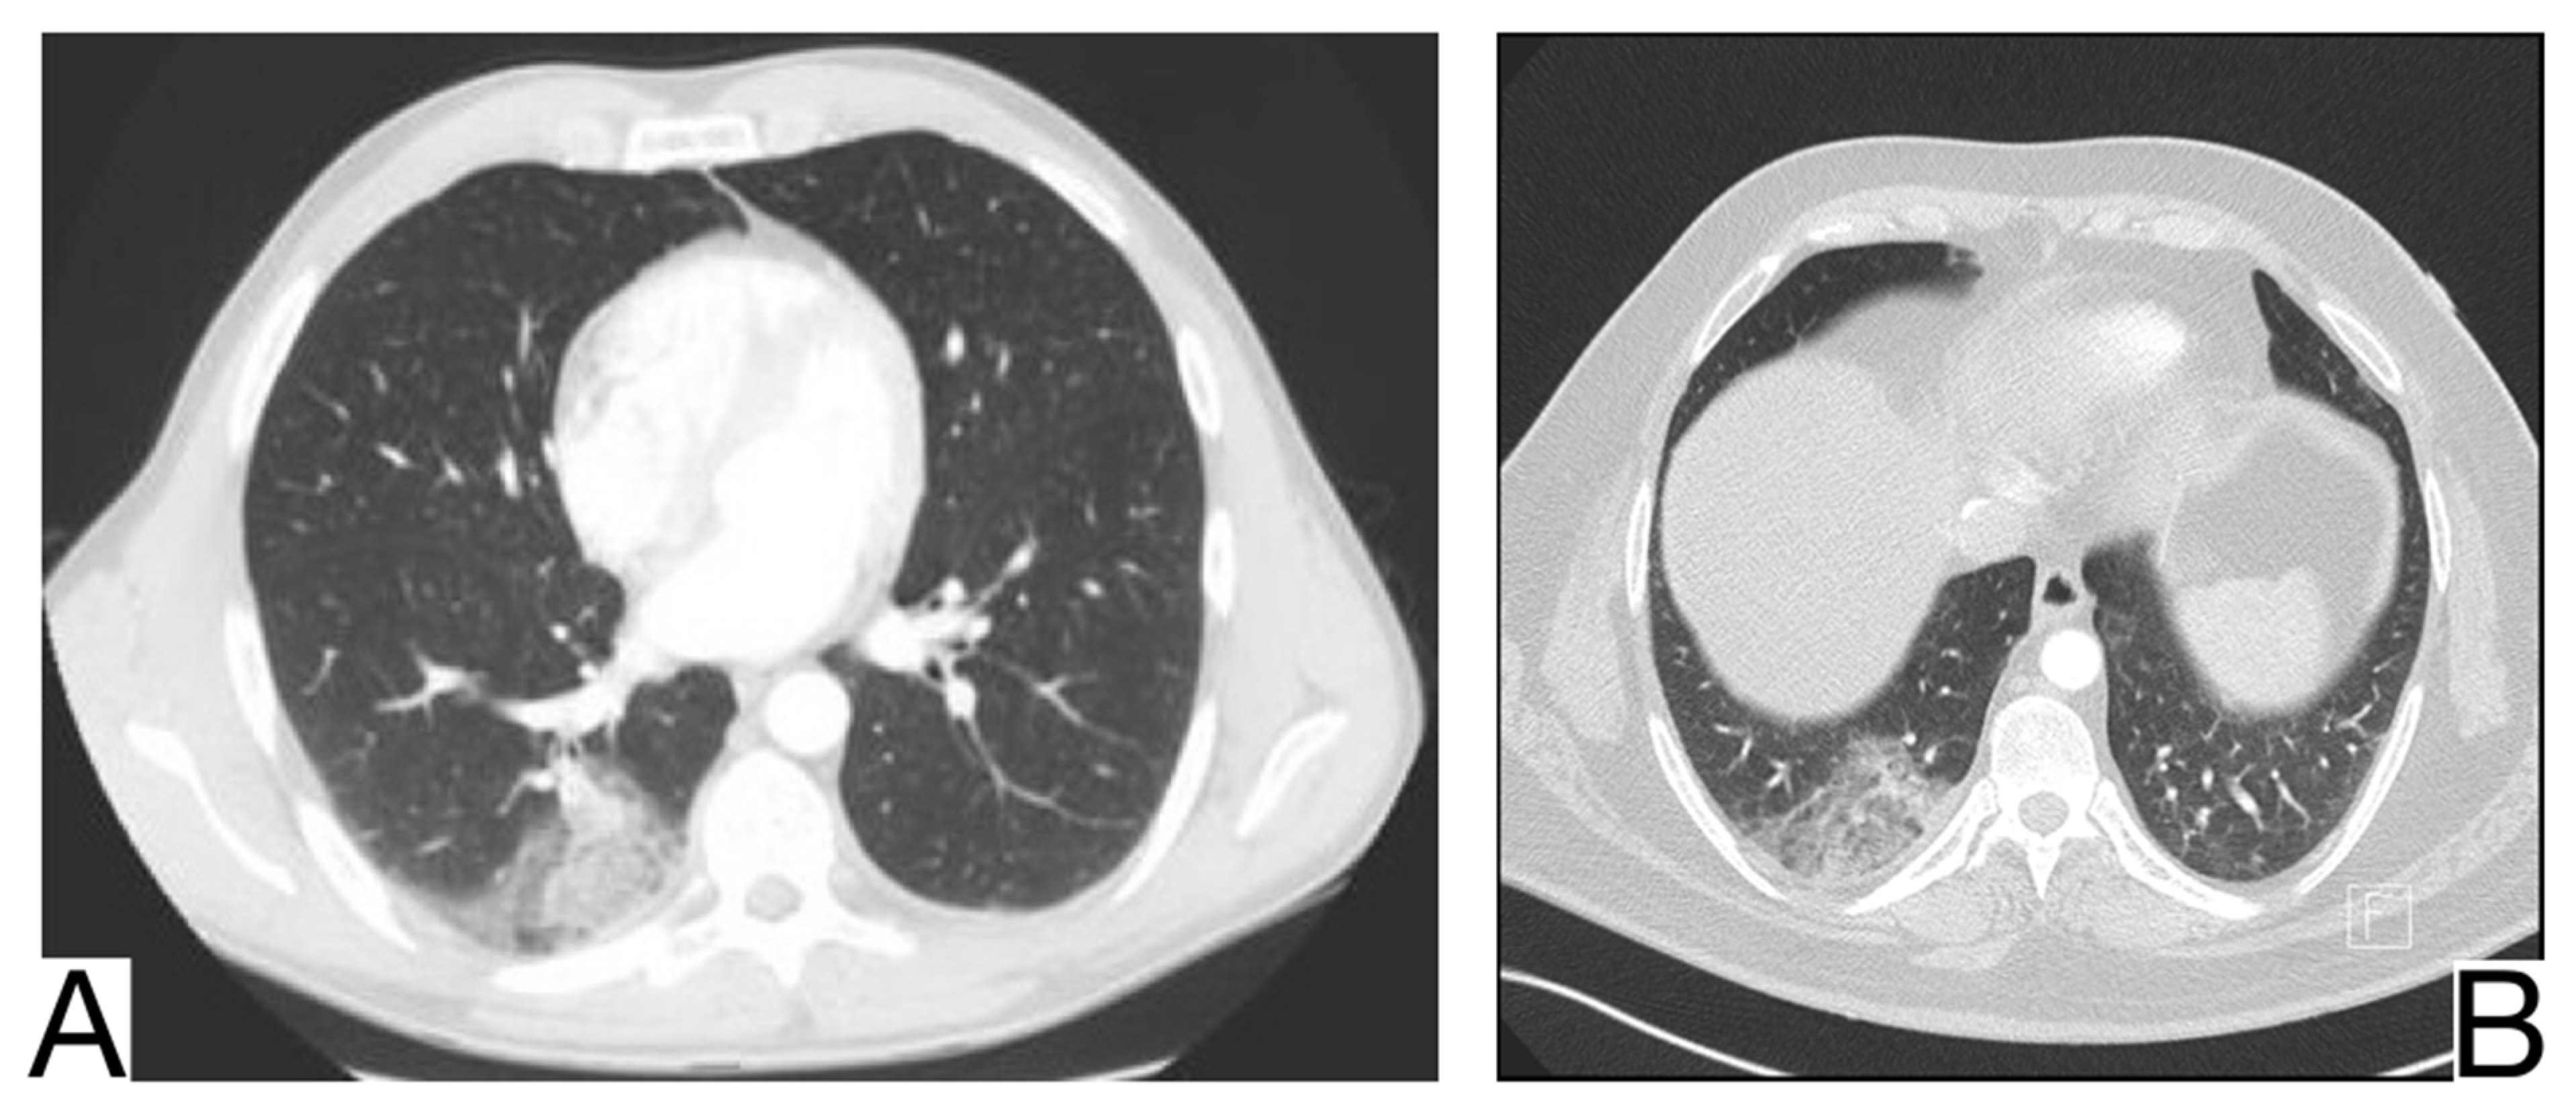

10.5.1. Acute Pulmonary Edema

10.5.2. Differential Diagnosis of COVID-19 Pneumonia with Acute Heart Failure